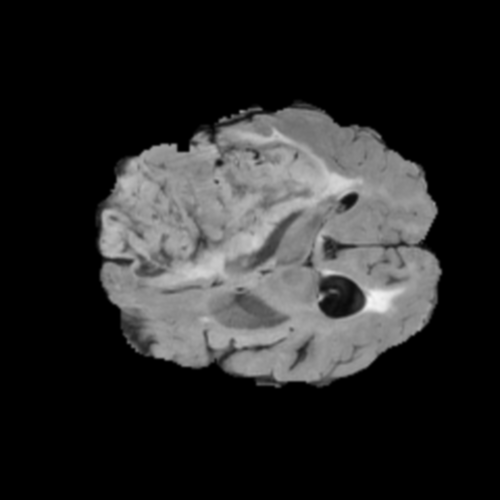

Ejemplos de Modalidades MRI

Visualización de las 4 modalidades de resonancia magnética y las segmentaciones de zonas tumorales utilizadas para entrenar el modelo

Glioma de Bajo Grado (LGG)

FLAIR LGG

FLAIR

T1ce LGG

T1ce

T2 LGG

T2

T1 LGG

T1